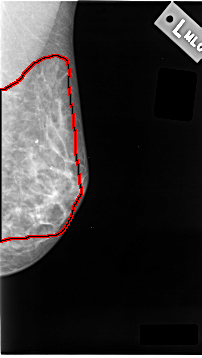

C_0039_1.RIGHT_CC

FILE: C_0039_1.LEFT_MLO.OVERLAY

TOTAL_ABNORMALITIES 1

ABNORMALITY 1

LESION_TYPE CALCIFICATION TYPE AMORPHOUS DISTRIBUTION DIFFUSELY_SCATTERED

ASSESSMENT 3

SUBTLETY 4

PATHOLOGY MALIGNANT

TOTAL_OUTLINES 1

BOUNDARY